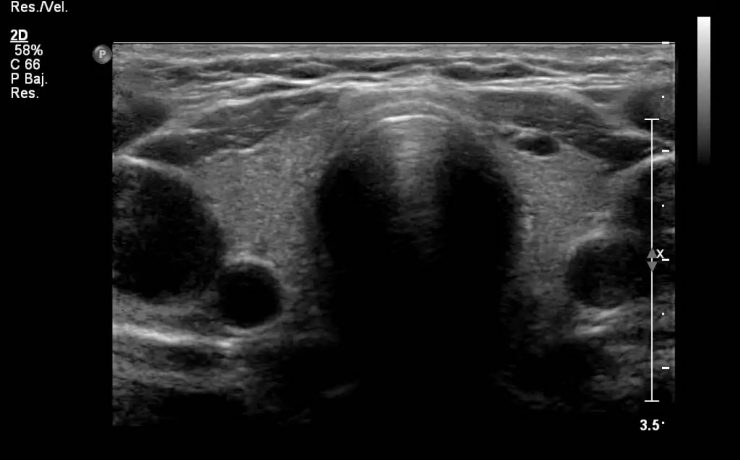

El parénquima esplénico tiene una ecogenicidad similar al hígado y menor que el riñón adyacente. Su valoración ecográfica es útil para confirmar la esplenomegalia y en el estudio de las lesiones esplénicas focales y de los traumatismos abdominales. El aumento del tamaño del bazo, que puede ser difícil de valorar